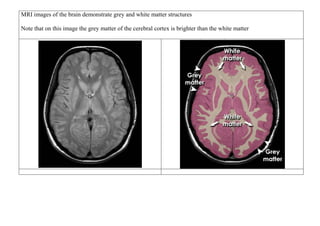

MRI images of the brain demonstrate grey and white matter structures

Note that on this image the grey matter of the cerebral cortex is brighter than the white matter